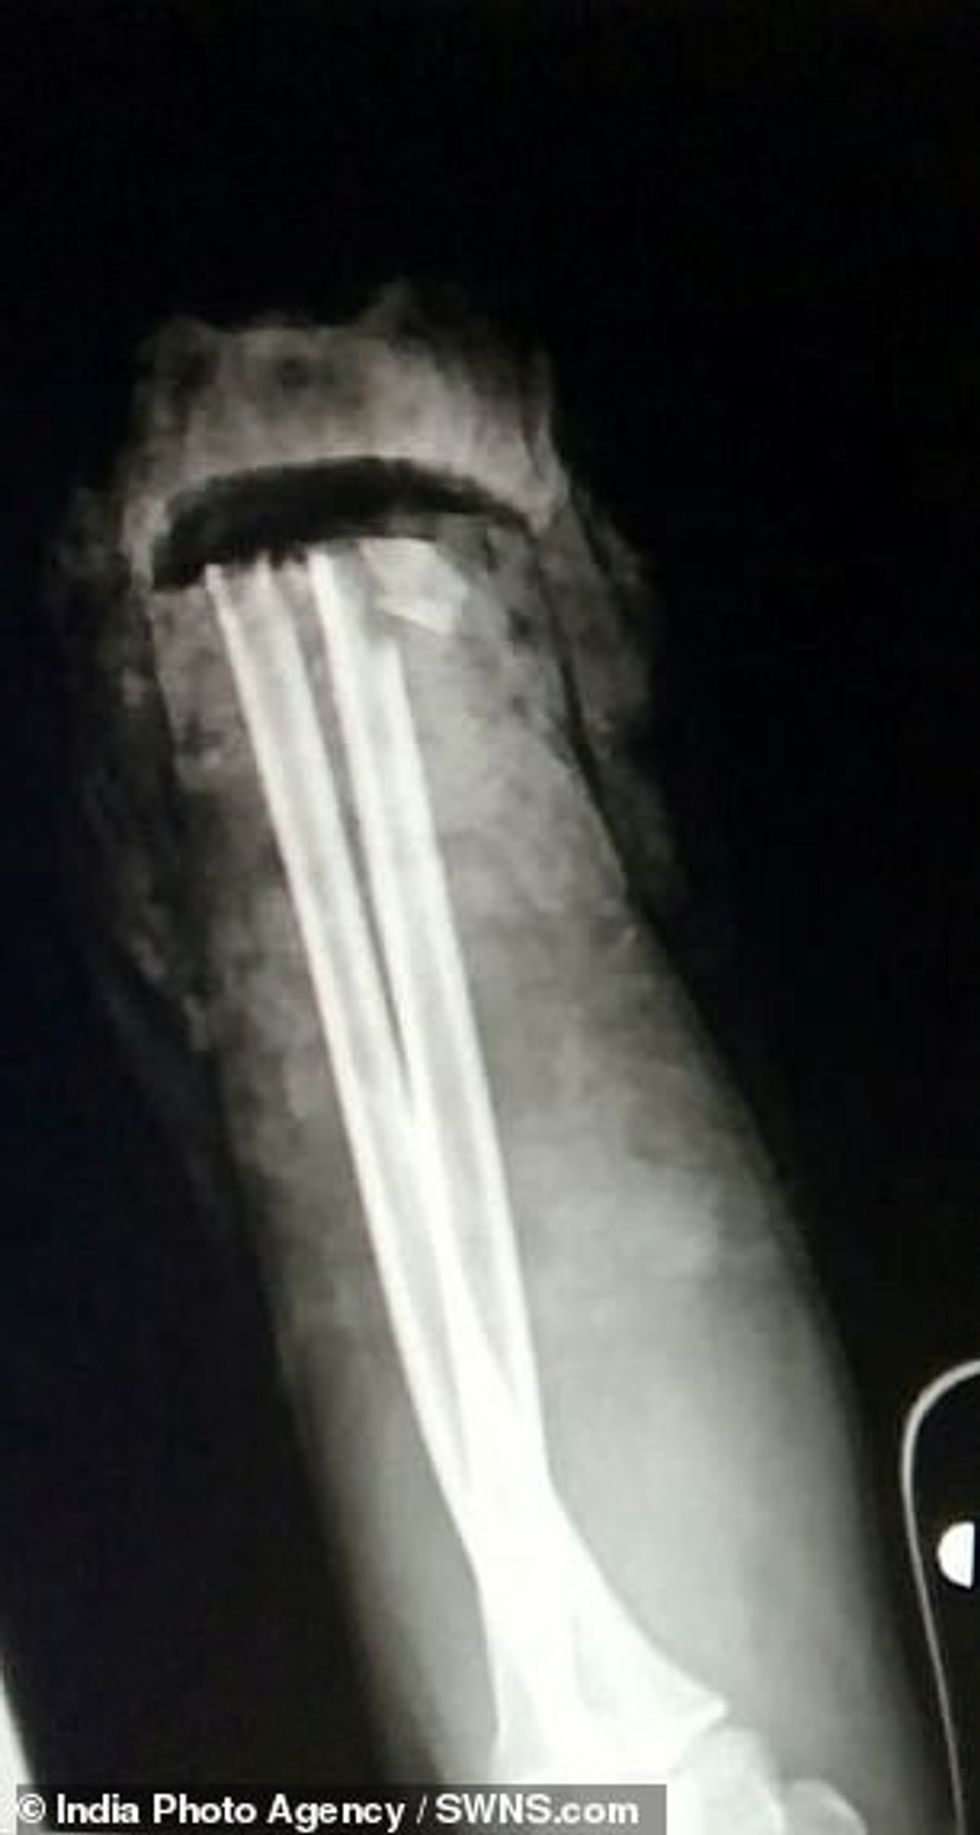

Për fat të mirë ishin disa persona që me urgjencë ia futën dorën e prerë në akull dhe më shpejtësi e dërguan në spital, ku pas intervenimit kirurgjik mjekët arritën t'ia ngjitin. /Telegrafi/